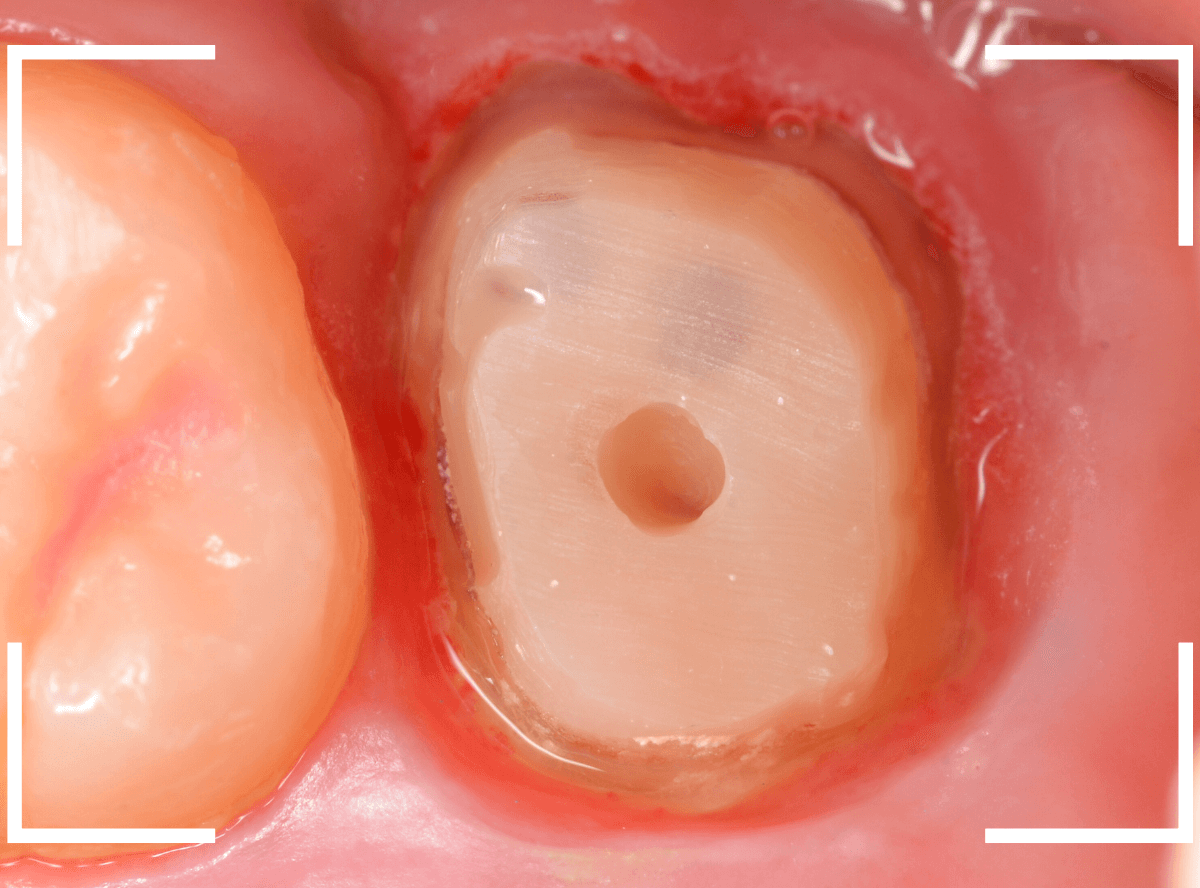

この状態で新しい土台(ファイバー・コア)の型を取ります。

模型上でファイバーコアを製作します。

ファイバーコアをsetし、歯の周りの歯肉が落ち着くまで、仮歯を入れて様子を見ます。

頃合いをみて、歯の型をとってさし歯の製作に移ります。

今回は、オール・ジルコニア・クラウンで製作することになりました。

最終setした状態です。

今回は厳しい条件でしたが、なんとか最終setまでする事ができました。